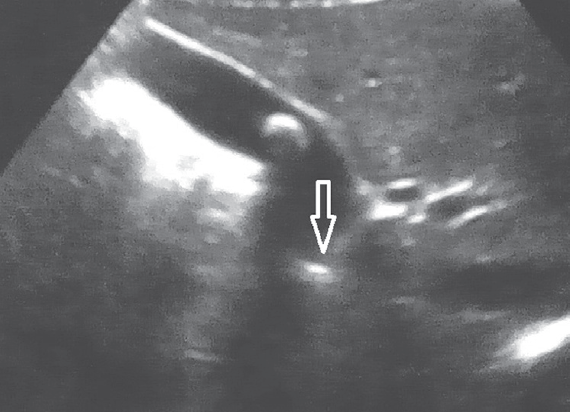

Проведенное в дооперационном периоде УЗИ гепатобилиарной системы выявило у всех пациентов с ЖКБ различные варианты деформации в области пузырного протока (рис. 4).

Рис. 4. Ультразвуковая картина деформированного пузырного протока

Fig. 4. Ultrasonic pattern of deformed cystic duct

Аналогичные изменения пузырного протока были выявлены и во время проведения оперативного лечения (рис. 5). Ни у одного пациента не было найдено конкрементов во внепеченочных желчных ходах.

Рис. 5. Интраоперационная картина деформированного пузырного протока

Fig. 5. Intraoperative picture of deformed cystic duct